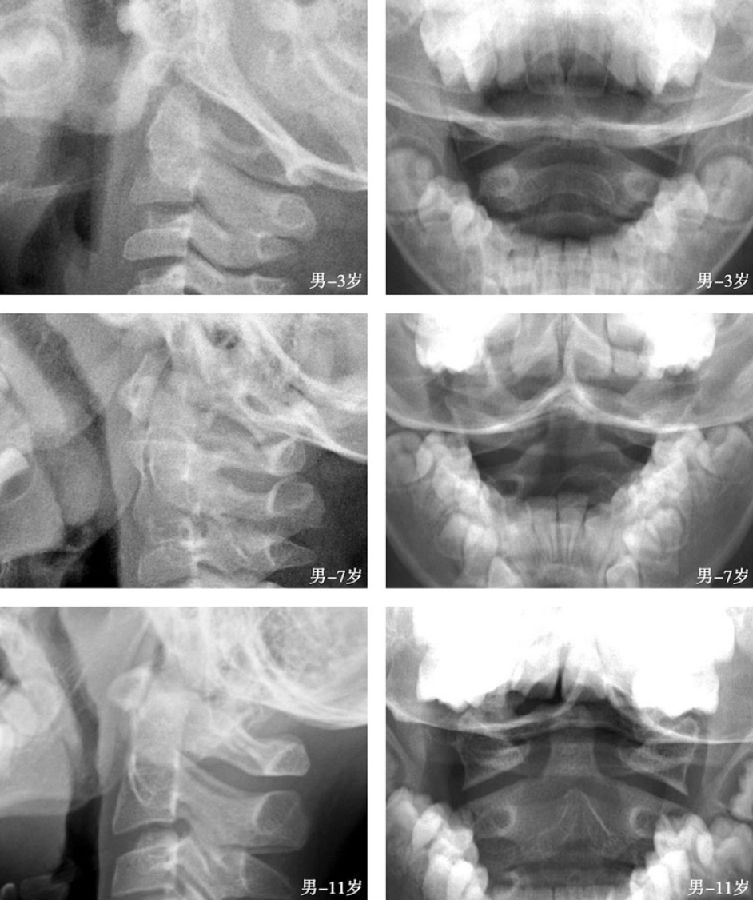

二、生长期正常表现

寰椎有3个骨化中心。在新生儿,X线仅能显示2个侧块的骨化中心。后者发育成寰椎后弓和侧块,4岁时后弓完成闭合。寰椎第3个骨化中心位于前弓,多在生后第1年出现。寰椎骨化中心常在5~9岁时融合。儿童侧块的骨化可先于枢椎椎体,与枢椎椎体相比,侧块明显向外侧移位,类似于寰椎骨折(假Jefferson 骨折)。(图2)

图2 生长期寰枢椎侧位及张口位

出生时,枢椎椎弓已有两个对称性骨化中心,4岁时融合。齿突骨化中心成对,脊索从其中部穿过。3~7岁时,齿突与椎体骨化中心融合,此时两个骨化中心之间仍有已退化的脊索和水平状的软骨联合存在。相互融合后,在此区域仍可残留骨硬化边、切迹或部分性裂隙,不能误认为是齿突骨折(图3)。齿突尖部单独骨化中心,可在出生时出现,但通常在第2年出现。齿突尖部骨化中心又称前寰椎或终末小骨,偶可孤立存在,但通常在12岁时与齿突骨化中心融合(图4)。终末小骨通常位于齿突尖部“V”形裂隙内,构成齿突尖部。

儿童颈椎活动度大于成人,在11~14岁时最大。侧位观,儿童颈部屈伸常有明显的枢椎与颈3间的相对移位,而颈3与颈4间移位不明显。约50%的7岁以下儿童,屈伸时枢椎后缘移位可达3mm或更大。屈曲位时,这种不均衡的移位最明显,称为“假性脱位”,此征象约在10岁时消失。8岁以前儿童颈椎后伸时,寰椎前弓可超过齿突尖2/3个齿突的宽度。